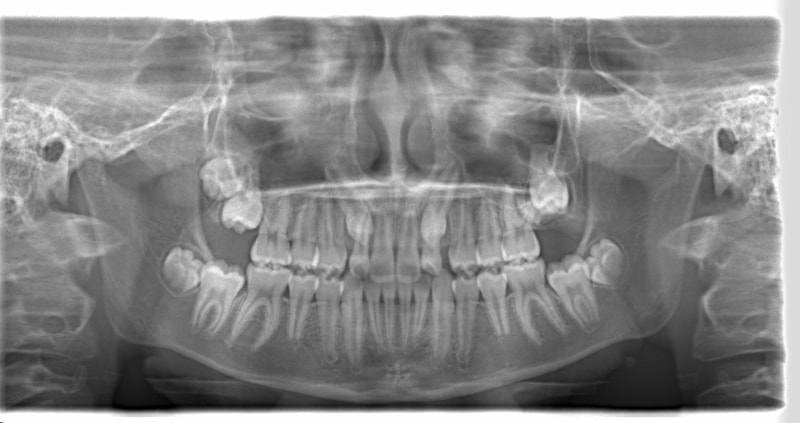

小児期ケース:反対咬合+上顎両側3番埋伏歯

(受け口+3番目の永久歯が左右両方とも埋まってしまい、はえてこない)

治療法:上顎急速拡大装置+クリアスナップ+フェイスマスク+上顎3番は開窓牽引CT写真にて位置確認

治療前

FX(フェイシャルアキシス)は85度なので東洋人の平均値に近く、下顎が前方に過剰成長するリスクは強くはありません。

しかしやはり上顎は劣成長で、下顎が優位な状態ではあります。

上下顎のギャップはありますが、顔面自体の幅径は良好な値を示していますので、スペース不足は拡大することによって解決できポテンシャルはあると考えられます。

左右の非対称もさほど強くありません。

骨年齢は実年齢よりも低めなので、今後下顎の旺盛な成長が見込まれます。

検査時のレントゲン分析では、上下顎の関係は、上顎の劣成長があり下顎前突傾向という値がでておりましたが、前歯ジャンプ後はフェイスマスクの効果もあり、上下顎の関係は正常化しています。

上顎が若干優位になっていますので、今後の下顎の成長のための貯金になっているくらいです。